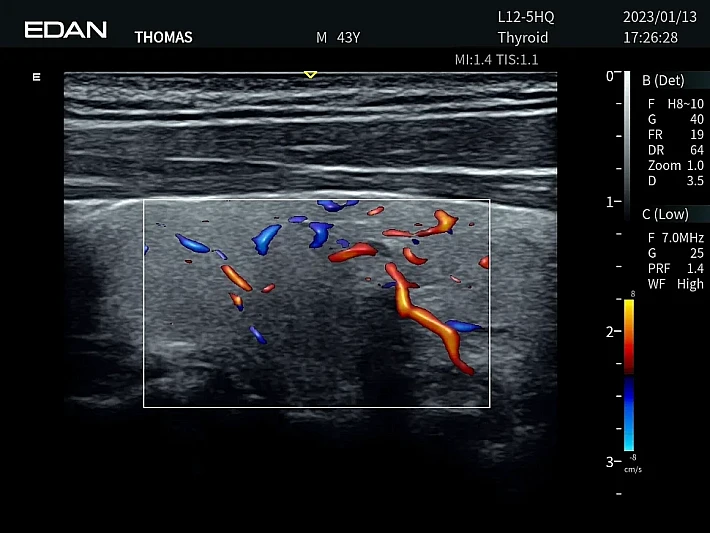

Медицинское оборудование и сервисное обслуживание